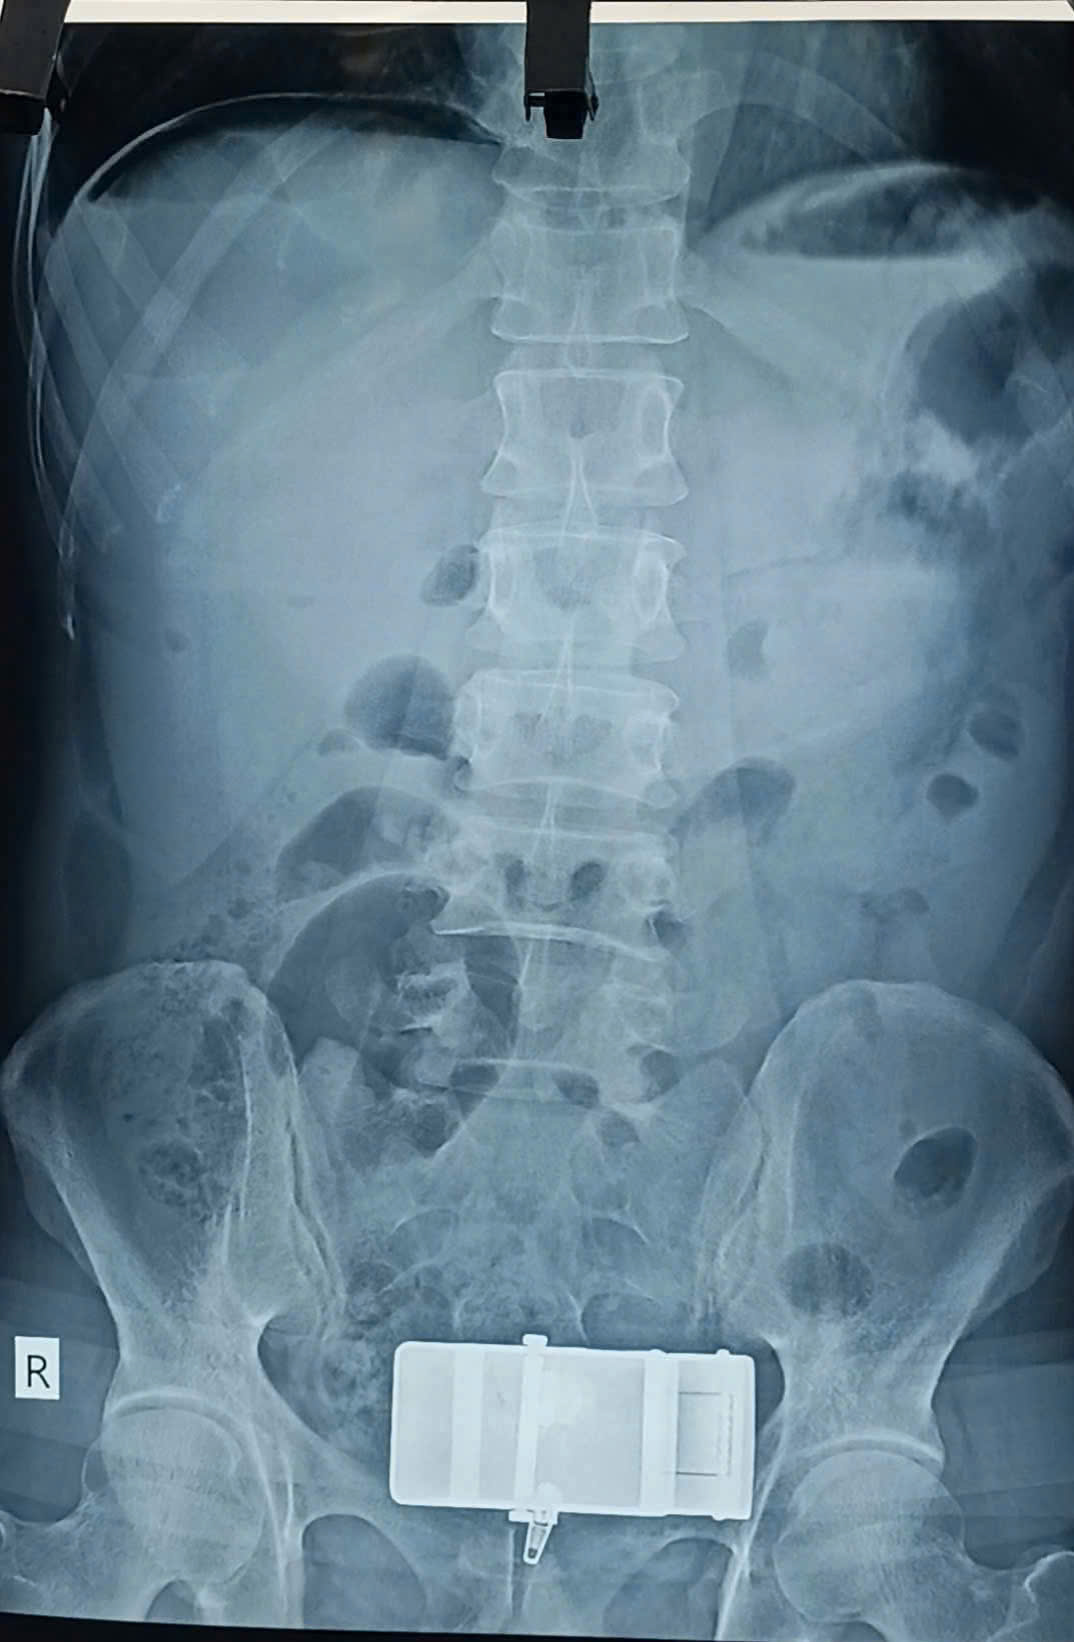

Trung tâm Y tế Khu vực Thuận An vừa tiếp nhận bệnh nhân nam, 47 tuổi, tiền sử viêm dạ dày và lạm dụng rượu bia. Bệnh nhân nhập viện khẩn cấp với cơn đau bụng dữ dội, chẩn đoán thủng ổ loét dạ dày. Sau khi được phẫu thuật nội soi kịp thời, bệnh nhân đã ổn định.